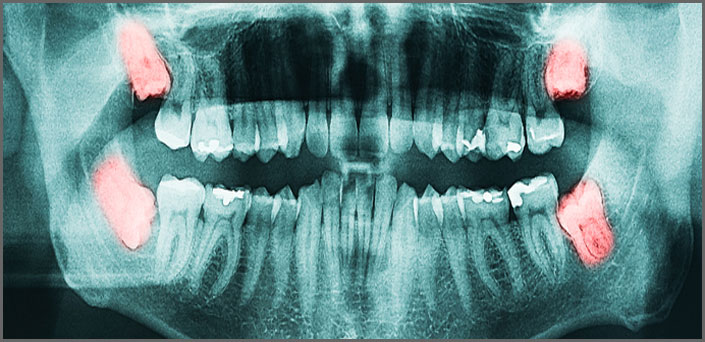

Η χειρουργική εξαγωγή αφορά δόντια ή τμήματα αυτών, τα οποία για να αφαιρεθούν απαιτείται μικρή τομή στα ούλα και αφαίρεση φατνιακού οστού.

Τέτοια δόντια είναι συνήθως οι ημιέγκλειστοι και έγκλειστοι φρονιμήτες, οι ρίζες νεογιλών δοντιών που αγκαλιάζουν τα μόνιμα και εμποδίζουν την ανατολή τους, σπασμένες ρίζες και ακρορίζια, δόντια με δυσπλασίες ή πολύ κεκαμμένες ρίζες, αγκυλωμένα δόντια κ.α.